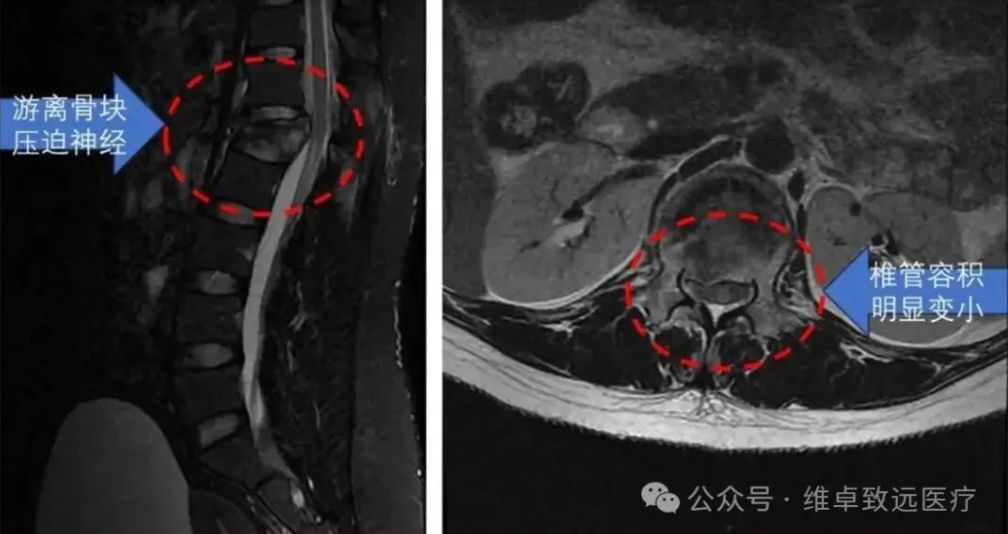

危急病情: 高坠致椎体爆裂骨折,神经受压命悬一线 术前X光:提示腰1椎体爆裂骨折 患者林女士(化名),29岁,因意外从近十米高处坠落,当即出现腰背部剧烈疼痛伴右下肢放射痛,被家人紧急送至广东医科大学附属医院脊柱外科二区就诊。 入院后,脊柱相关影像学检查结果显示:患者腰1椎体爆裂性骨折,部分碎裂骨块向后突入椎管,导致椎管明显狭窄,后方脊神经受到直接压迫。 术前 MRI: 提示有游离骨块向后移位压迫神经, 椎管容积明显变小 据主治医生介绍,该患者病情危急且复杂:不仅椎体及附件粉碎严重,存在骨折块移位刺激神经的情况,左侧椎弓根更出现断裂,传统手术中精准置入椎弓根螺钉的难度极大。若手术操作不当,可能导致永久性神经损伤、下肢瘫痪等严重后果,对手术的精准度和安全性提出了极致要求。 术前 CT: 提示腰 1 椎体爆裂骨折,右侧椎弓根断裂 (图中红色箭头所示) 技术革新: 星航导航系统,构建全流程数字化手术平台 传统脊柱内固定手术中,尤其是面对骨折粉碎、解剖结构异常的复杂病例时,椎弓根螺钉的置入往往依赖医生的临床经验和术中X光片的反复透视,如同“盲人摸象”,不仅存在置钉位置不佳的风险,还可能损伤神经血管,且术中辐射暴露较多。 为突破这一技术瓶颈,广东医科大学附属医院前瞻性引进由维卓致远创新研发的星航骨科手术导航系统。该系统由中国工程院唐佩福院士牵头,汇聚顶尖骨科专家与工程师智慧,历时四年研制而成,已斩获多项国家发明专利及创新医疗器械认证。 其核心优势并非单一导航功能,而是构建了“影像交互-手术规划-精准导航” 的全流程数字化手术平台,通过底层技术融合,系统性提升脊柱外科疑难重症的诊疗能力,彰显了我院紧跟医疗科技前沿的战略眼光。 精准手术: 手术规划 + 实时导航,实现 “所见即所得” 维卓致远导航系统手术规划 本次手术的核心技术亮点在于星航导航系统 “打破时空限制” 的精准导航能力。术前,林颢教授带领医疗团队将患者腰椎CT数据导入系统,利用其手术规划模块,在三维模型上自动识别骨折椎体,精准规划每颗螺钉的最佳植入路径、直径及长度,并从数字耗材库中预选匹配螺钉进行模拟植入,形成个性化 “数字手术蓝图”。 与传统导航需依赖昂贵笨重的术中三维扫描设备(如O型臂)重新获取影像匹配不同,星航导航采用多模态配准技术,直接将术前三维CT规划与术中普通二维X光片精准匹配,实现三维术中导航,如同为手术视野加载“GPS定位”与“实时透视”功能。医生可在导航屏幕上实时查看虚拟螺钉路径与实际解剖结构的完美叠加,真正实现“所见即所得”的精准操作。 12月9日,在充分术前准备后,手术正式启动。在星航导航系统的实时引导下,林颢教授凭借二十余年丰富的手术经验,娴熟完成导针置入、开路、螺钉固定等操作,每一步都精准避开重要神经和血管。 整个置钉过程流畅高效,不仅大幅减少术中透视次数、降低辐射暴露,更确保了内固定的最佳生物力学稳定性。术后复查显示,所有椎弓根螺钉位置精准,骨折复位满意,椎管容积有效恢复,患者神经压迫症状迅速缓解,目前恢复状况良好。 术后复查:椎弓根螺钉位置完美,骨折复位良好 专家解读: 技术赋能,开启脊柱外科精准治疗新时代 骨科中心主任、脊柱外科专家魏劲松教授表示:“对于林女士这类复杂爆裂性骨折病例,椎弓根置钉的容错率极低。星航导航系统提供的毫米级精准指引,显著提升了手术安全性与疗效可预期性。此次成功实践,不仅为我们开展更复杂的脊柱畸形矫正、微创手术积累了宝贵经验,更为科室临床技术创新与科研发展开辟了新思路。” 林颢教授强调,星航导航系统的成功应用,是骨科手术从“经验依赖”向“数据驱动、精准可视”转型的重要里程碑。其术前规划让手术方案更优化,术中多模态配准技术则破解了传统导航对昂贵设备的依赖难题,真正实现精准、微创、高效的诊疗目标,对患者、医生与医院均具有重大意义。” 左二为林颢(主刀手术中) 作为粤西地区医疗高地,广东医科大学附属医院始终勇于拥抱医疗科技前沿,持续提升诊疗服务水平。此次粤西首例星航骨科导航系统辅助脊柱手术的成功开展,是医院技术创新与学科建设的又一重要成果。 未来,医院将继续探索推广数字化智能手术技术,让更多医疗创新成果惠及广大患者,为推动骨科手术精准化、微创化、智能化发展贡献 “附院力量”。